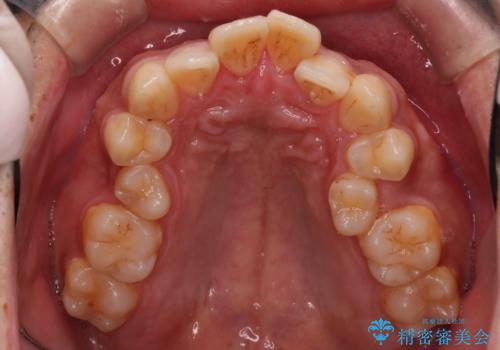

【審美ワイヤー】奥歯のガタガタを治したい

- 歯並びの凸凹を主訴に来院されました。

スペースが必要なため、抜歯を行なって治療を行いました。

奥歯の捻れが強く治療期間がかかりましたが、綺麗な仕上がりに満足していただきました。